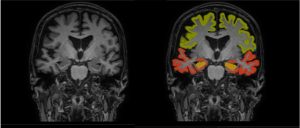

Icobrain tracks brain volume changes to evaluate disease progression, providing precise and relevant change metrics.

Dementia MRI with segmentation

Brain MRI scans from Stanford and the Michael J Fox Foundation‘s landmark Parkinson’s Progression Markers Initiative (PPMI) – launched in 2010 to follow people, with and without PD, over time to learn more about how disease starts and changes – were evaluated in terms of volumetric patterns and correlated to corresponding clinical scores for motor and cognitive function.

The results show that regional brain volumetry assessment can serve as an important biomarker in prediction and differentiation of Parkinson’s disease patients at risk for motor and, or, cognitive disability progression.